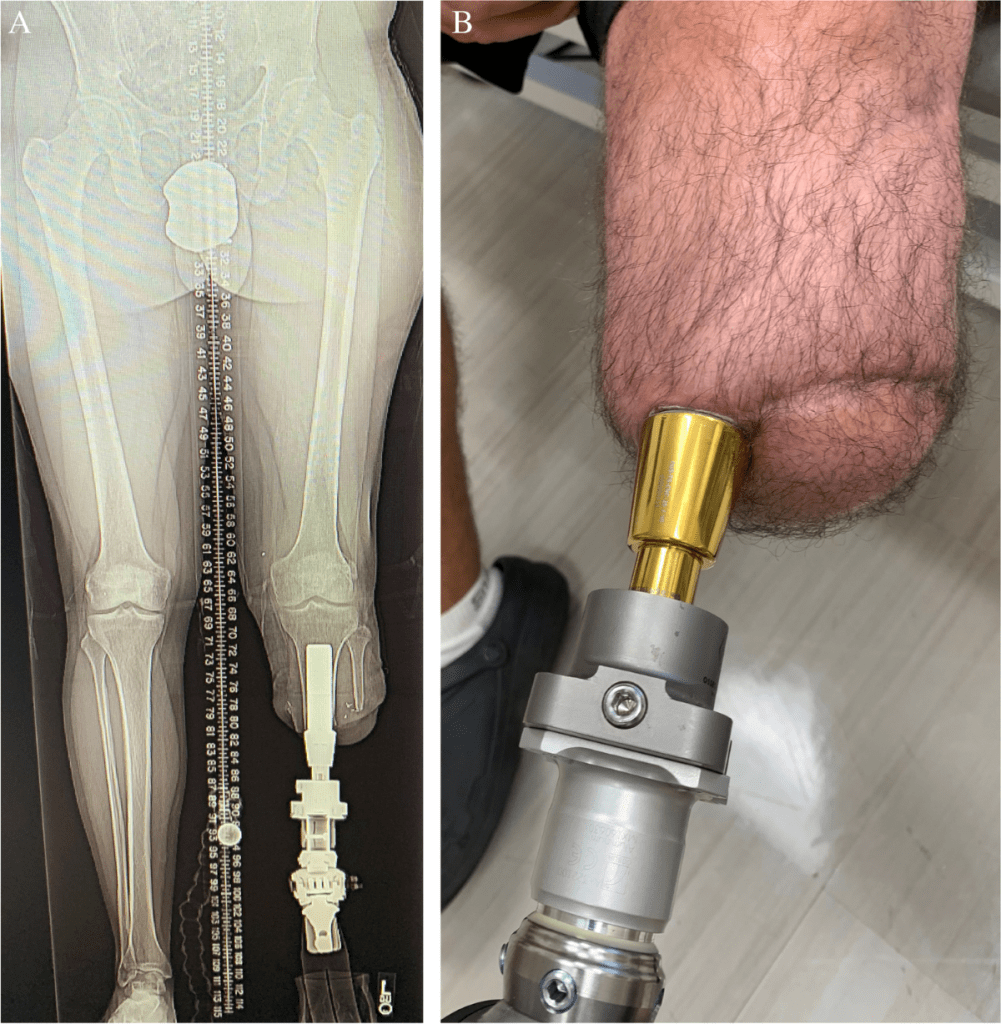

Autre avantage : le port de la prothèse sera complètement différent. Fini les frottements sur la peau — la tige sera intégrée directement dans le tibia. (Je vous ai mis quelques photos en annexe.)

C’est une bonne illustration de la méthode, bien que son application diffère d’un individu à l’autre.